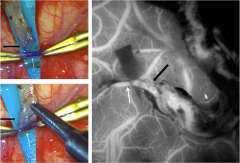

Moyamoya Anastamosis collage

UCLA Health's multidisciplinary collaboration expands the breadth of treatment options for complex neurovascular cases

Advances in vascular imaging technology are opening up additional options for stroke prevention and cognitive health.  Conditions that reduce the blood flow to the brain, including ICAD and moyamoya disease, can cause recurrent strokes and significant cognitive and neurological impairment. Surgery to re-open or bypass blocked arteries may help, but experience shows that a personalized treatment plan based on imaging and other clinical data is needed to provide patients the best possible outcomes.

The UCLA Stroke Center provides comprehensive diagnostic and therapeutic care for simple and complex vascular disorders through multidisciplinary teams that work closely with patients and their referring physicians. “We offer the expertise not just of individuals, but of our center as a whole,” says neurosurgeon Geoffrey Colby, MD, PhD, director of cerebrovascular neurosurgery at UCLA. “A good part of the success of the procedures we perform comes from the care that’s provided before and after, through the immediate recovery period and beyond.”

The center’s neurosurgeons treat patients with complex vascular lesions, often using revascularization to avert ischemia and then monitoring patients to provide ongoing treatment for the disease. “Vanishingly few health care systems in the world offer a full range of surgical revascularization options for stroke patients,” says neurosurgeon Anthony Wang, MD, who specializes in cerebrovascular, pediatric and complex cranial-base surgeries. “At UCLA, we are able to offer the complete range of surgical revascularization options, and the rare expertise of our team allows us to tailor a plan for each individual patient’s needs.”

Expertise that goes beyond the ‘typical patient’

Moyamoya disease typically affects young people, even children, who are seemingly healthy until the condition is discovered following a stroke. After a stroke, moyamoya patients often “sit at a tipping point,” says Dr. Wang. “They have the potential both for an excellent recovery or for disastrous progression.” To better ensure that a patient tips toward recovery, researchers at UCLA are testing non-invasive interventions to protect vulnerable regions of the brain adjacent to the initial stroke. For instance, stimulation of certain nuclei using high-intensity focused ultrasound appears to have a neuroprotective effect. Transcranial direct-current stimulation is currently in trials for patients with acute strokes caused by large vessel occlusion, and may prove useful for moyamoya patients as well.